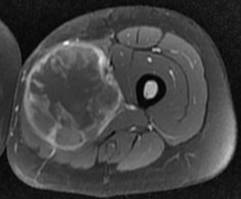

Histiocytofibrome malin. Noter l’aspect hétérogène en T2, avec prise de contraste hétérogène

Histiocytofibrome malin